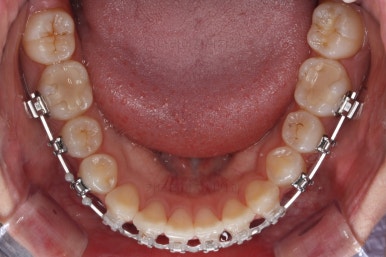

부산치아교정잘하는곳 키다리아저씨치과에서 치료를 시작한지 3개월째의 모습입니다.

솔직히 이정도만 해도 만족하시고 치료를 종료해달라는 분도 있긴 있어요.

하지만 교정치료를 시작한 이유가 앞니 가지런하게 하는 것도 있지만 왼쪽, 오른쪽 교합을 맞추는 것에도 있기 때문에 지금부터는 맞지 않는 교합에 초점을 두었어요.

추가로 사용한 장치는 바로 미니스크류(마이크로 임플란트) 장치입니다. 화살표를 보시면 잇몸뼈에다가 매우 작은 크기의 스크류를 식립해서 전체 치열을 밀고 당기고 해주는 거에요.

보시다시피 왼쪽 치열들의 교합이 뭔가 틈새가 많고 정확하지 않기 때문에 해당 부분에 미니스크류를 해서 교합을 맞춰주기로 했답니다.

아직 위아래 중앙선도 어긋나 있고, 교합도 아직은 미흡하네요.

계속 당겨주고 비대칭을 맞춰주고 하게 됩니다.

미니스크류를 이용해서 전체 치열을 움직인지 6개월 정도 지난 시점입니다.

교합도 많이 좋아졌고 자연스럽게 중앙선도 맞아졌어요.